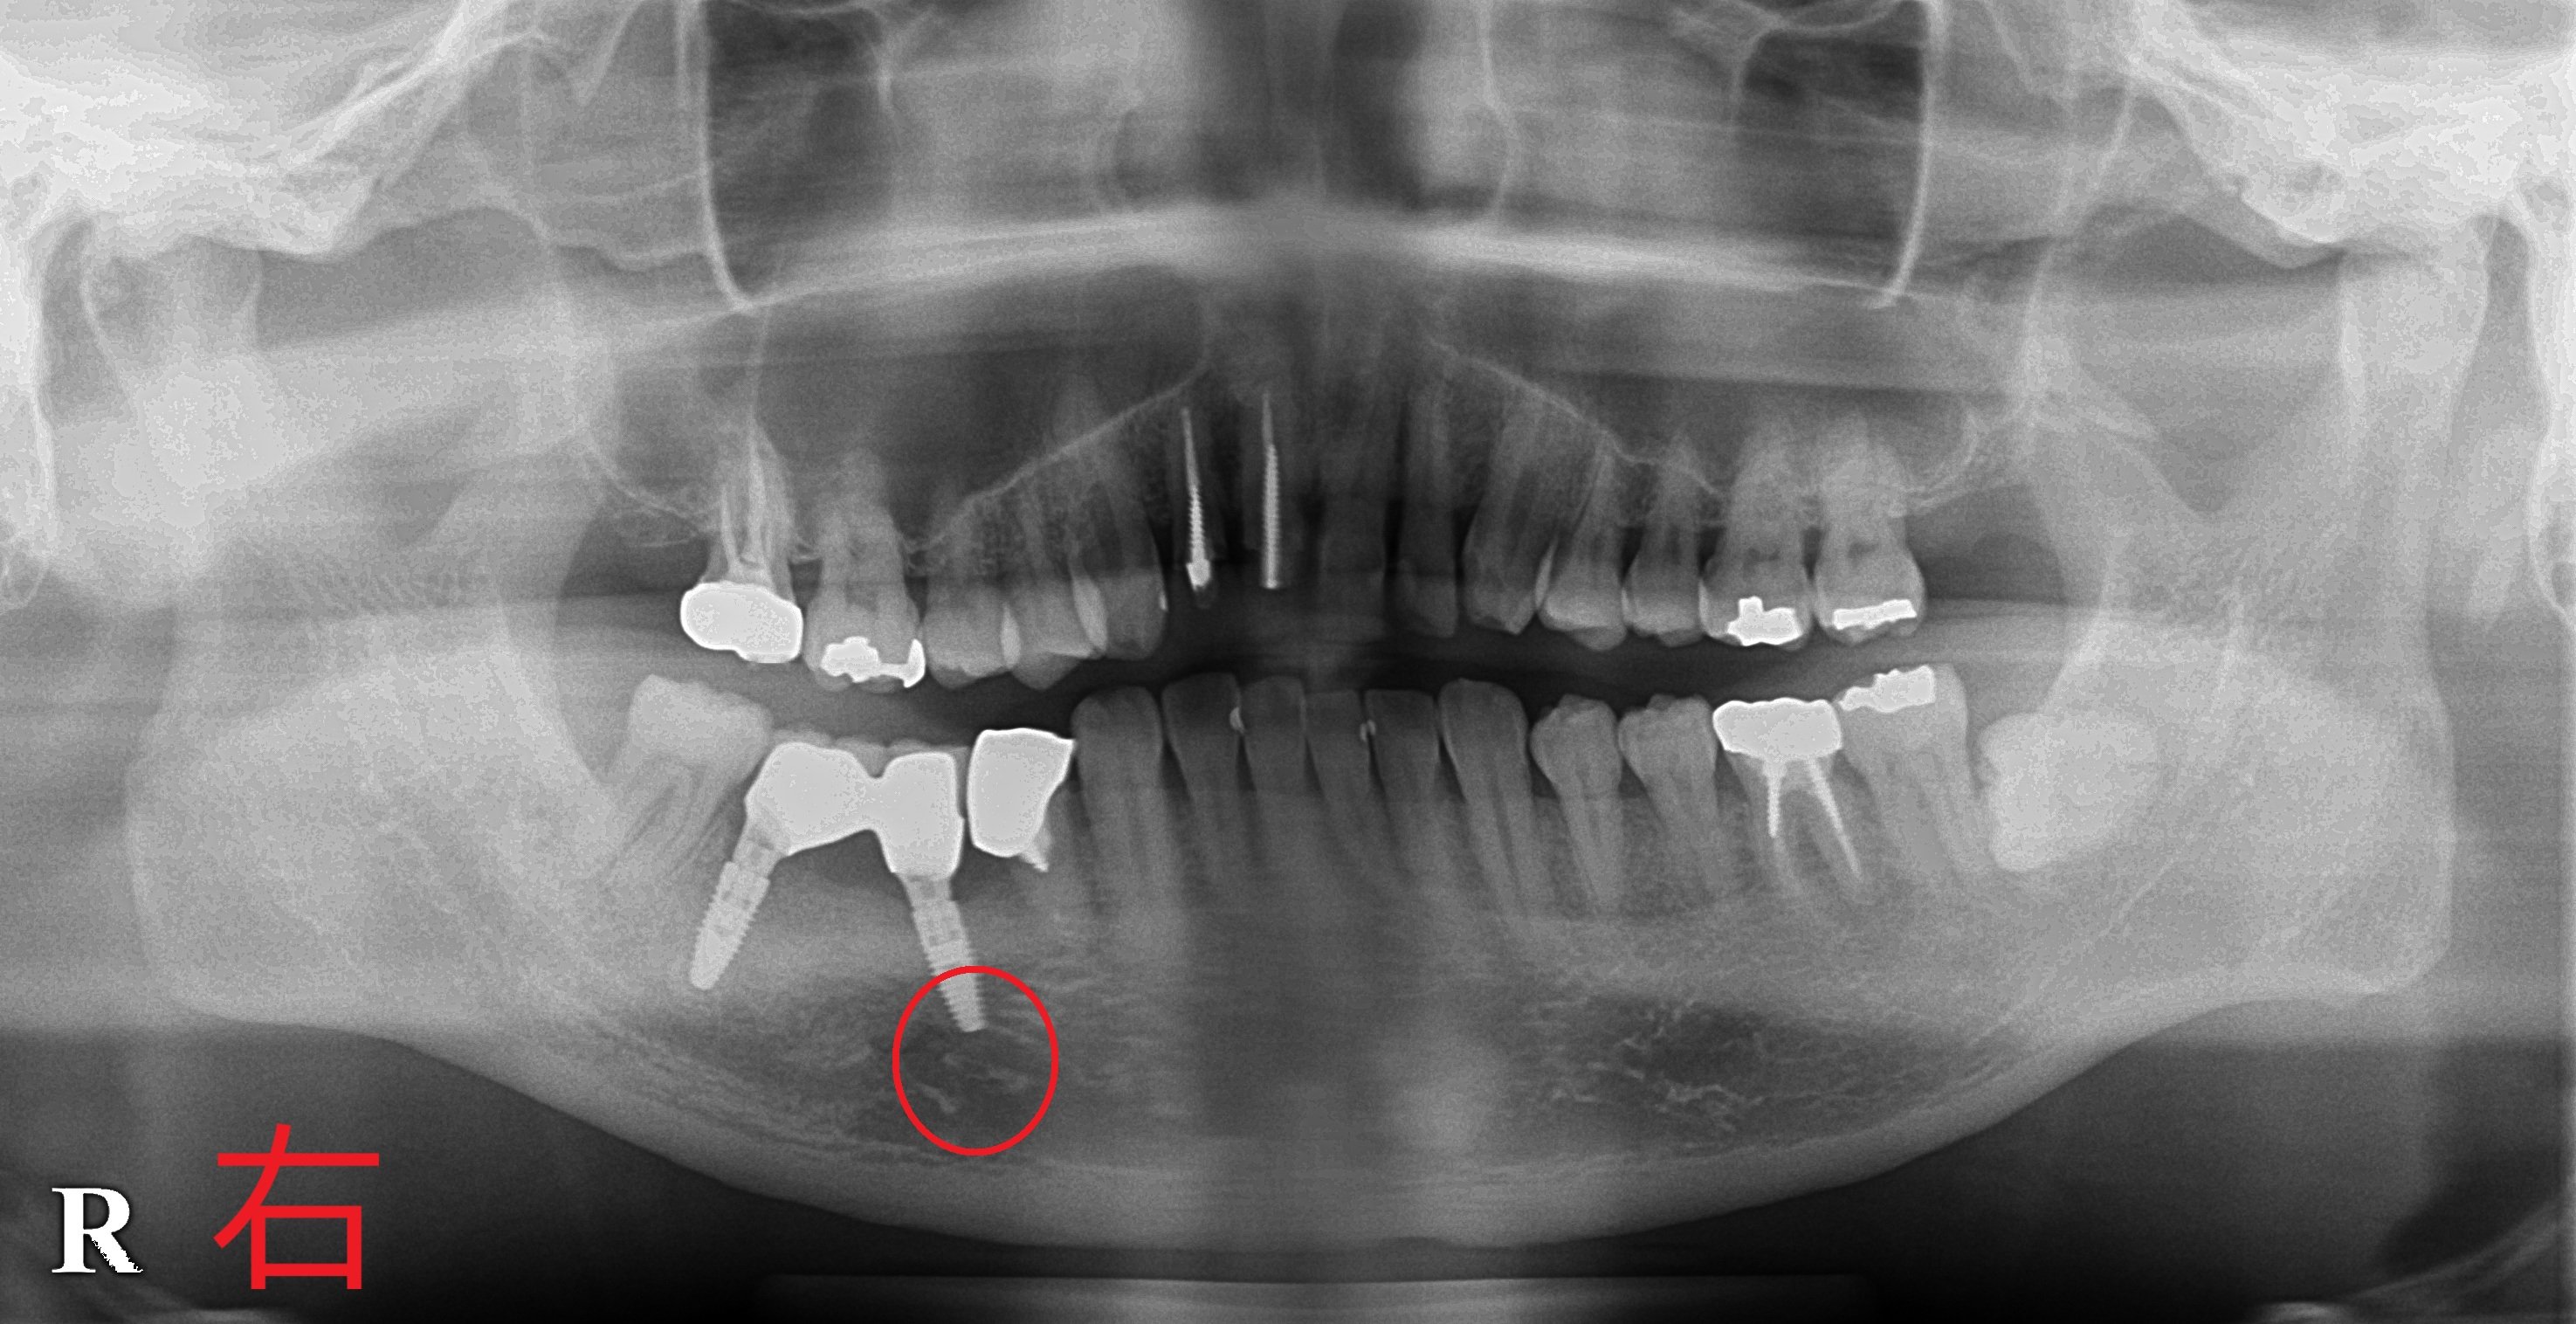

後方の破折歯を抜歯後、そこに1本、その前方に1本のインプラントを埋入し、約3か月後にセラミック製の冠を装着しました。

【インプラント術後のレントゲン】

一見すると2本のインプラントが平行に見えないかもしれませんが、赤い円で示された位置には下歯槽神経の出口があり、この神経を傷つけると麻痺が生じる可能性があります。そのため、神経を回避する方向にインプラントを傾斜埋入しております。

この程度の傾斜埋入であれば、長期的な予後や咀嚼機能に支障はありません。

当院では、手術前にCT撮影を行い、神経の位置を正確に把握したうえで十分なシミュレーションを実施し、安全性に配慮したインプラント手術を行っております。